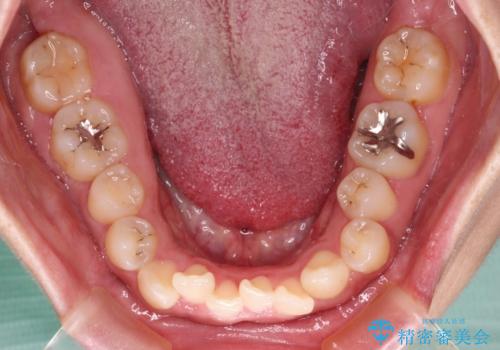

- 前歯の叢生と八重歯を気にして来院された患者様です。

目立たない装置を希望とのことで、インビザラインにて矯正治療を行うこととしました。

インビザライン単体で改善することも可能ですが、八重歯とその後方にある歯列を確実移動させないと、上下正中がずれてしまう可能性があります。

インビザライン単体での治療ではなく、カリエール・ディスタライザーという補助装置を併用して、より確実性を上げることとしました。

補助装置で八重歯を解消しながら、並行してインビザラインで歯列を整えることとしました。